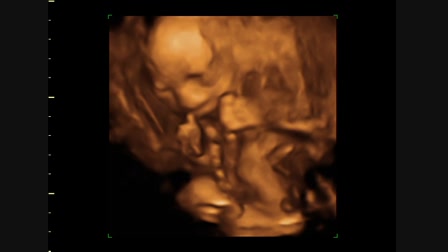

Hédi kacag :D